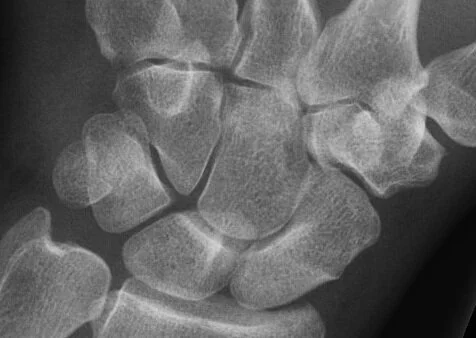

Pain over Hypothenar Eminence A 50 year old woman presenst with pain over the hypothenar eminence after falling onto an outstretched hand.What is the injury? Click here to find out Posted on April 22, 2021 by NUEM Blog and filed under Wrist and tagged pain wrist fall.